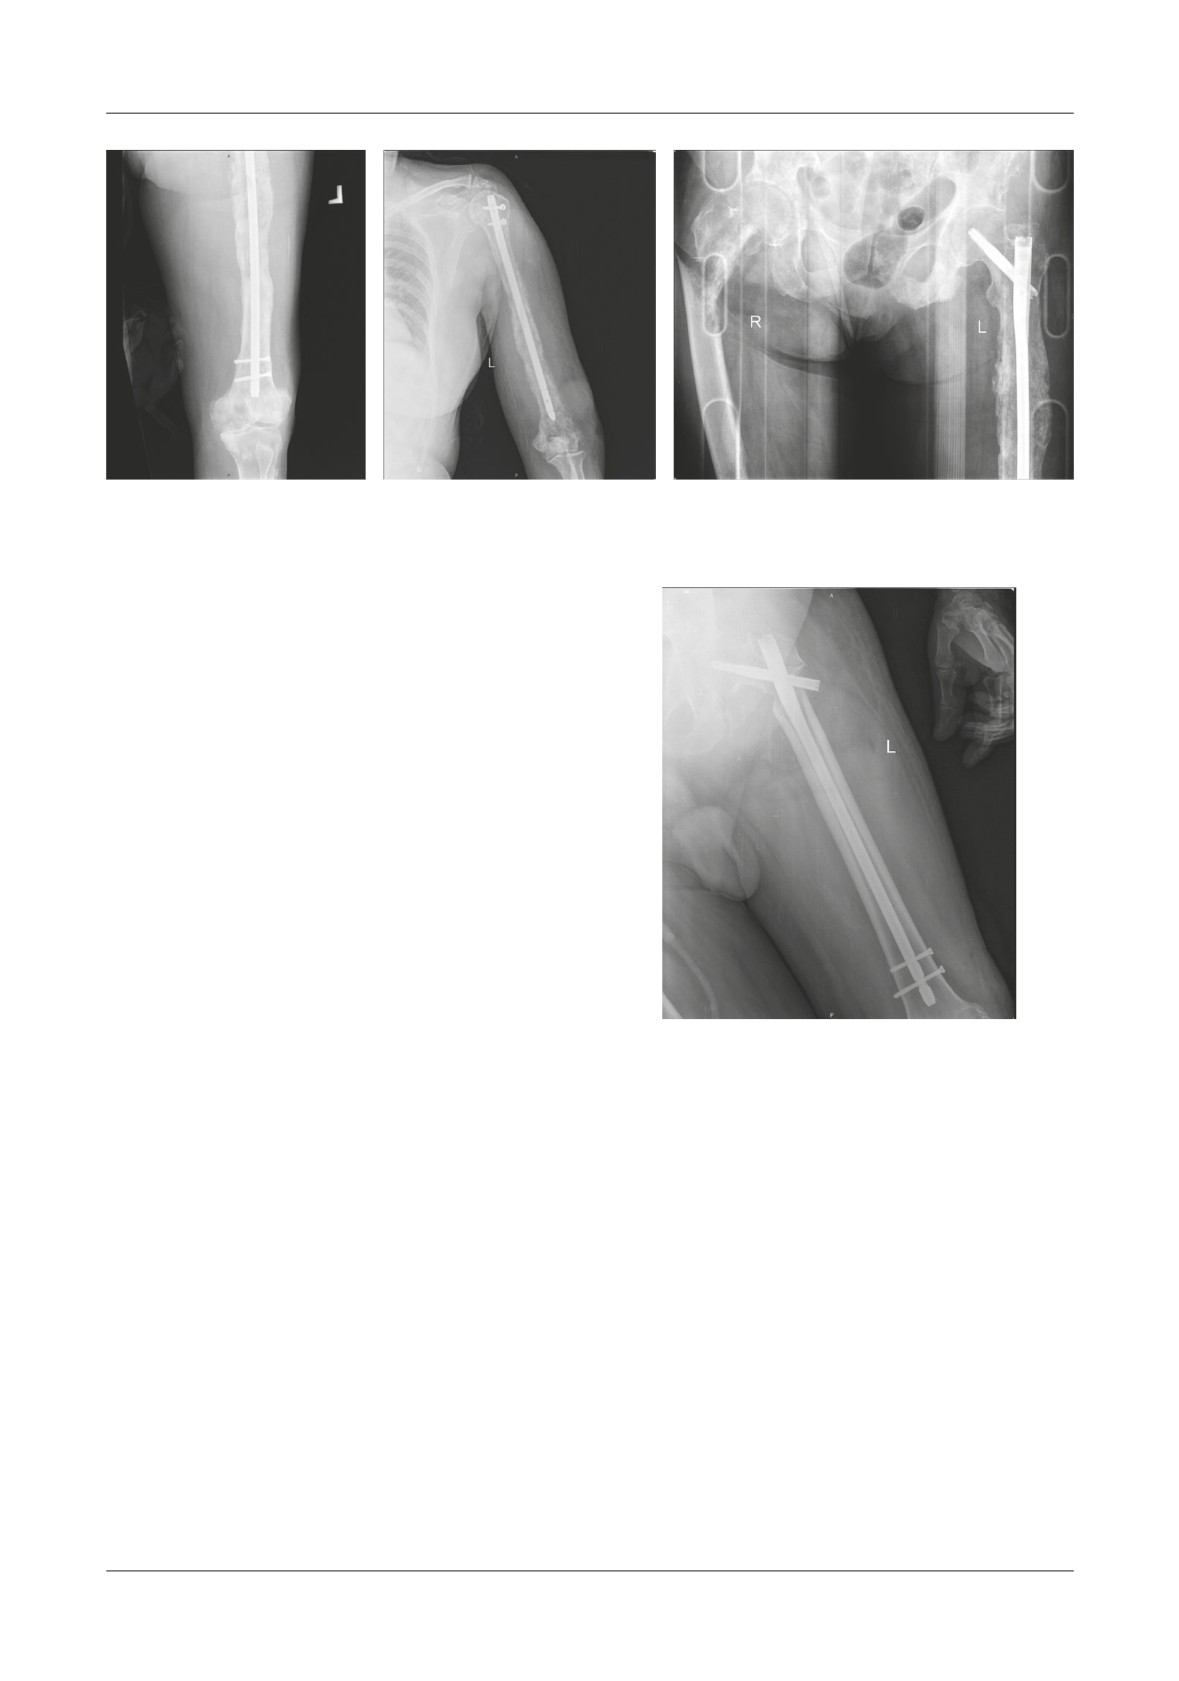

Figure 2. A,B. Axial CT images that reveal the lytic bone area from within the femoral neck as well as the zone

of the pathologic fracture. C. Coronal CT reconstruction shows the tumor mass that expands the muscles

surrounding the proximal femoral area. D. 3D CT reconstruction meant to carefully show if there are any

other fractures that expand distally. E. AP X-ray of the right coxo-femural joint

A

B

Figure 3. A. AP X-ray of the coxo-femural joint which shows loosening of the cervico-cephalic

nail. B. AP X-ray of the distal femur that shows both of the distal screws being broken.

Figure 4. A. Te first pathologic fracture occurred in the sub trochanteric area and it was stabilized with a long gamma nail.

B. After 8 months the patient presents at the hospital with pain in the left arm - a humeral shaft fracture is depicted on x-rays

and intramedullary nailing is done to the humerus. C. After another 10 months the patients suffers a sub trochanteric fracture

to the contralateral femur

Figure 5. Te result of our surgery can be seen

fracture is depicted on x-rays and intramedullary nailing

on this AP X-ray of the patient’s left hip